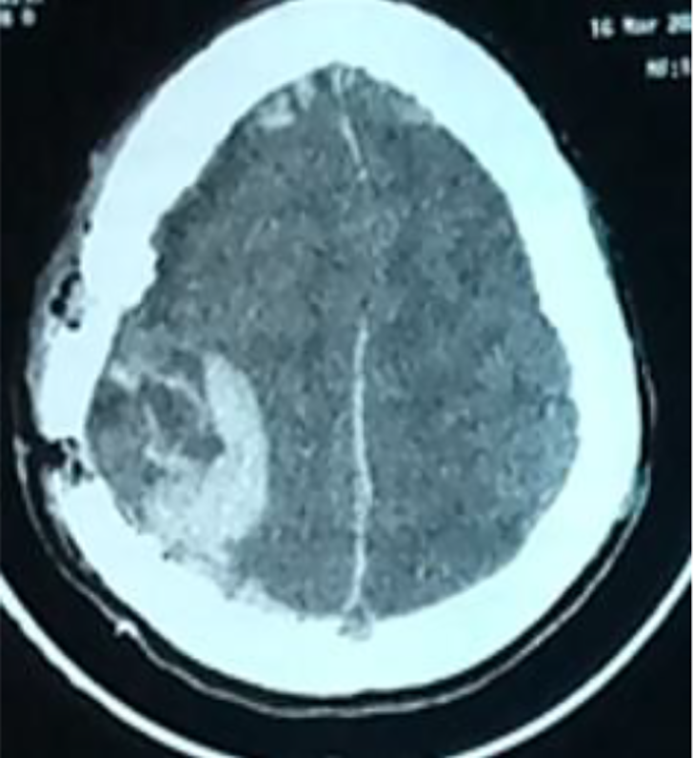

As part of the investigation into his facial oedema and headaches, a cerebral CT scan was carried out two days after his admission to the hospital, showing two extra dural haematomas on the right frontal side measuring 7.1 mm and the right parietal side measuring 27 mm, with no signs of involvement (Fig. 1) or associated bone fracture, and an abnormally thick diploid (Fig. 2).

Fig. 1. Parenchymal axial CT section showing a 27 mm right parietal extradural hematoma.

He underwent emergency surgery, and surgical evacuation of the hematoma after a right parietal flap was made. The bone was hemorrhagic, with no fractures or signs of soft tissue trauma. The patient was transfused with packed red blood cells and 5 platelet concentrates. The postoperative course was marked by neurological deterioration and the appearance of right anisocoria, prompting an emergency CT scan, which revealed an intraparenchymal hematoma associated with a 10 mm thick subdural fronto-parieto-occipital haematoma and diffuse cerebral oedema (Fig. 3), necessitating emergency surgery. The patient was transferred to the intensive care unit and died of multi-visceral failure. This work has been reported in line with the Surgical Case Report (SCARE) criteria [4].

Fig. 3. Post-operative CT scan showing an intra-parenchymal haematoma with a subdural haematoma lamina, diffuse cerebral oedema, and meningeal hemorrhage.